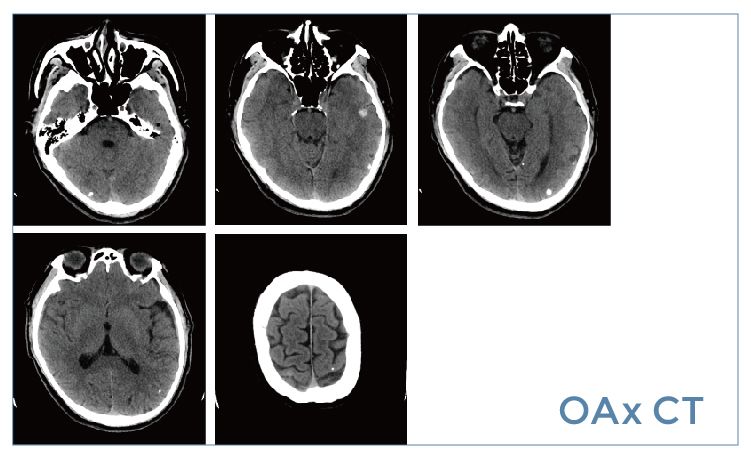

【朗润影像档案】20190614磁共振影像病例结果讨论

【朗润影像档案】磁共振影像病例分享(编号20190614)